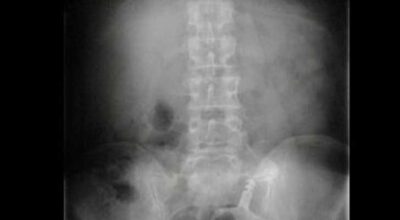

Esta recopilación de imágenes recoge alguna de las situaciones más estrambóticas que se han podido dar en una sala de rayos X. Todas ellas tienen algo en común: Son objetos extraños para el cuerpo humano que, de alguna manera han encontrado una vía de entrada, pero se han perdido a la hora de encontrar la de salida.

Muñecas de juguete descabezadas, botellas, armas, frascos, botes de plástico, teléfonos y hasta una cinta de casete pueden encontrarse en esa suerte de “punto limpio” al que ha quedado reducido el interior de los afectados.

No sabemos, ni juzgamos, la forma o los motivos por los que terminaron atrapados en dichas partes del cuerpo, pero estamos convencidos de que algún doctor estuvo al borde de la carcajada cuando se encontró con casos tan llamativos e inverosímiles como estos ¡Ver para creer!